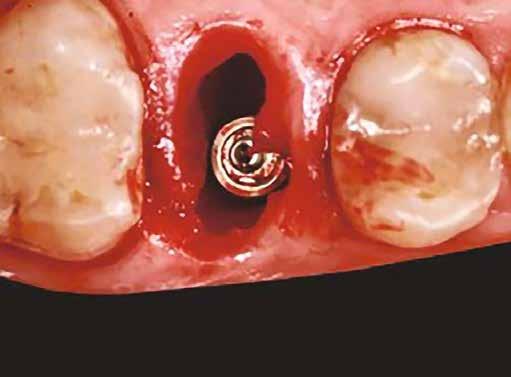

Egy 47 éves páciens jelentkezett nálunk egy alsó, hátsó foghiánnyal, ahol jelentős csontfelszívódást tapasztaltunk a moláris fogak korábbi eltávolítása miatt (1. ábra). Két implantátum körül is volt ínyrecesszió, illetve a keratinizált íny mennyisége minimális volt (kevesebb, mint 1 mm). 4 hónappal az implantációt követően ínykorrekciót végeztünk.

Helyi érzéstelenítést végeztünk a műtéti területen artikain és 1:100 000 adrenalin segítségével. A recipiens területet előkészítettük, élesen disszekciót végeztünk, hogy egy izomtapadástól mentes periosteum ágyat képezhessünk. Ettől disztálisan két párhuzamos parakresztális metszést végeztünk egy 15C-s szikepengével, majd a metszéseket egy

2–5. ábra: A metszések és a deepitelizáció. – 6–9. ábra: Félvastag lebeny. – 10. ábra: A nyelezett ínylebeny „bepróbálása”.

horizontális metszéssel kötöttük össze (2–5. ábra). A metszések hosszát és a köztük lévő távolságot minden esetben a lágyszövet augmentációhoz szükséges keratinizált szövet határozza meg. A lebeny deepitelizációját egy 15C-s szikepengével végeztük (6. ábra). Ezt követően félvastag lebenyt preparáltunk (7. ábra). A lebenyt apikálisan, az alapjáról belső, felületes metszéssel felszabadítottuk, hogy passzívan áthelyezhessük és rögzíthessük, feszülés nélkül. Meziális irányba 180 fokkal átforgattuk (8–9. ábra). A meziális papillát alagúttechnikával (tunnelling technique) készítettük elő a graft befogadására (10. ábra). Az így kialakított lebenyt a recipiens ágyban rögzítettük az újonnan kialakított vesztibulum alapjánál 5-0 nem felszívódó PTFE (Coreflon, IMPLACORE) varratokkal. A graftot behajtottuk az ínyszél alá és meziális oldalon rögzítettük PTFE varratokkal (11–14. ábra)